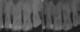

Figure 6.2.a : Parodontite chez un patient de 45 ans. De nombreux dépôts de tartre et de plaque dentaire sont visibles à la surface des dents. La gencive présente une certaine inflammation.

Figure 6.2.b : Sur ce même patient, les lésions osseuses sont visibles radiographiquement avec une perte osseuse horizontale d’environ 20 %.

Figure 6.3.a : Parodontite chez un patient de 25 ans. La gencive n’est pas rétractée et seule une certaine inflammation des tissus est visible, alors que le cas est sévère.

Figure 6.3.b : Les lésions osseuses sont importantes et 80% du support osseux est détruit sur certaines dents.